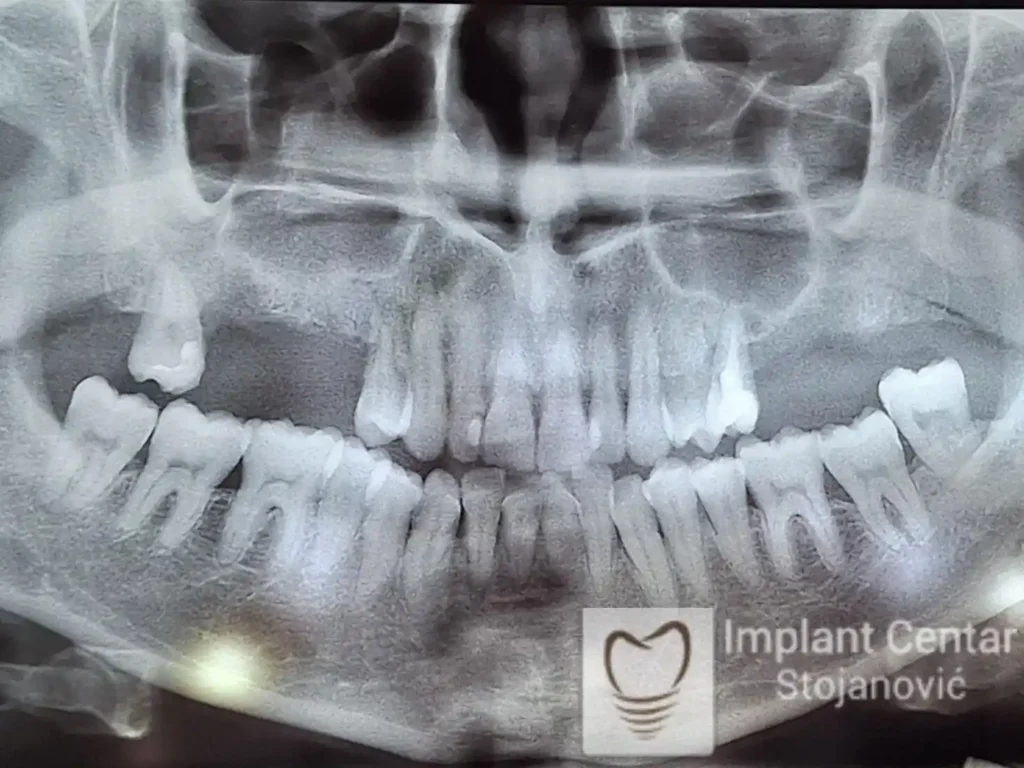

Na slici 1. i slici 2. prikazan je izgled pacijenta pre početka terapije – klinički i rendgenološki.

Nakon vađenja zuba, ugrađeni su implantati. Na slici 3 prikazan je ortopan snimak sa ugrđenim implantatima. Tokom perioda osteointegracije, pacijent je bio zbrinut fiksnim privremenim krunicama na implantatima, koje su izrađene samo dva dana nakon hirurške intervencije.